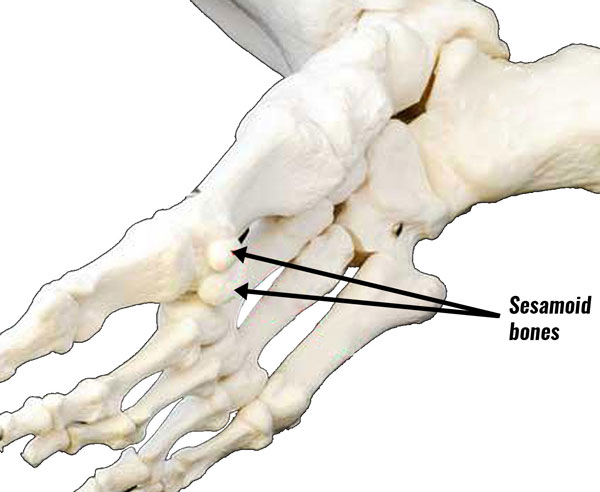

Анатомия: Блоки и сесамовидные кости в деталях